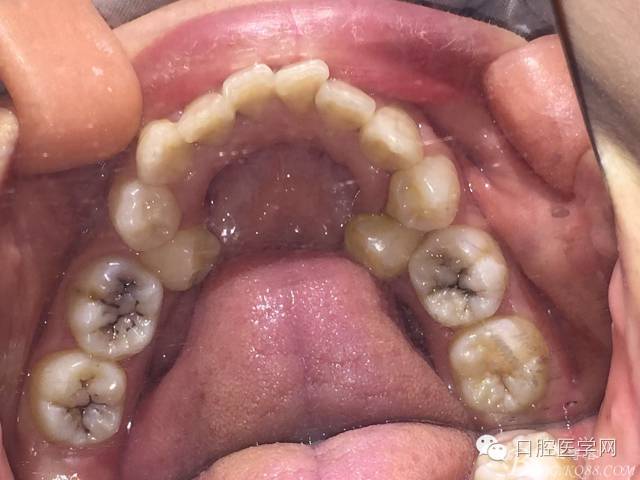

患者 女性 21 主訴:牙齒不齊,面突影響美觀。

重度擁擠減數(shù)雙尖牙時UL4頰根遠(yuǎn)中彎曲,導(dǎo)致斷根,為防止進(jìn)一步創(chuàng)傷,又怕后期間隙關(guān)閉不順,應(yīng)用擴(kuò)大針將殘根牽引出